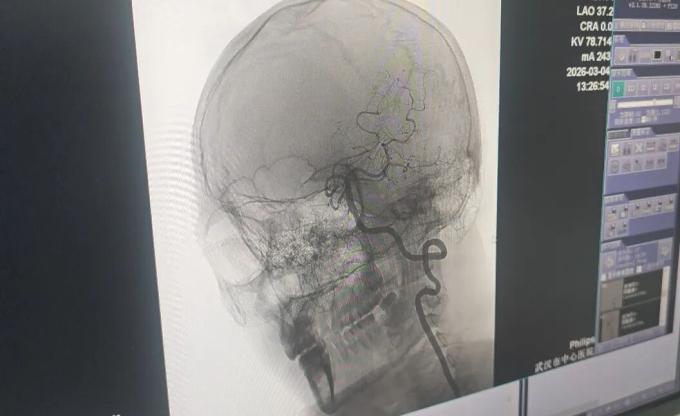

Đội ngũ y tế đã can thiệp và tái thông thành công mạch máu bị tắc của anh Vương. Ảnh: Li Huizi

Tại bệnh viện, các bác sĩ thần kinh chẩn đoán bệnh nhân tắc nghẽn mạch máu lớn cấp tính và chỉ định truyền thuốc tiêu sợi huyết qua tĩnh mạch. Tuy nhiên, chỉ nửa giờ sau, tình trạng anh Vương chuyển biến xấu. Anh rơi vào hôn mê sâu, đồng tử trái giãn, mất phản xạ ánh sáng, liệt hoàn toàn nửa người trái kèm liệt mặt, lưỡi và mất khả năng ngôn ngữ. Bác sĩ tiến hành chụp mạch máu và phát hiện vết rách ở lớp nội mạc động mạch đốt sống gây rối loạn huyết động nghiêm trọng, hình thành cục máu đông làm tắc mạch. Bác sĩ Hùng Vĩ, Trưởng khoa Thần kinh, giải thích rằng phần mô lộ ra từ lớp nội mạc tổn thương đã kích thích tạo huyết khối nhanh chóng, dẫn đến bế tắc hoàn toàn lưu lượng máu.

Êkíp cấp cứu lập tức chuyển người bệnh đến phòng can thiệp mạch. Nhận thấy động mạch đốt sống chưa tắc nghẽn hoàn toàn, các chuyên gia quyết định thực hiện thêm phương pháp tiêu sợi huyết đường động mạch. Sự kết hợp đồng bộ này đã tái thông dòng máu chính xác, cứu sống bệnh nhân.